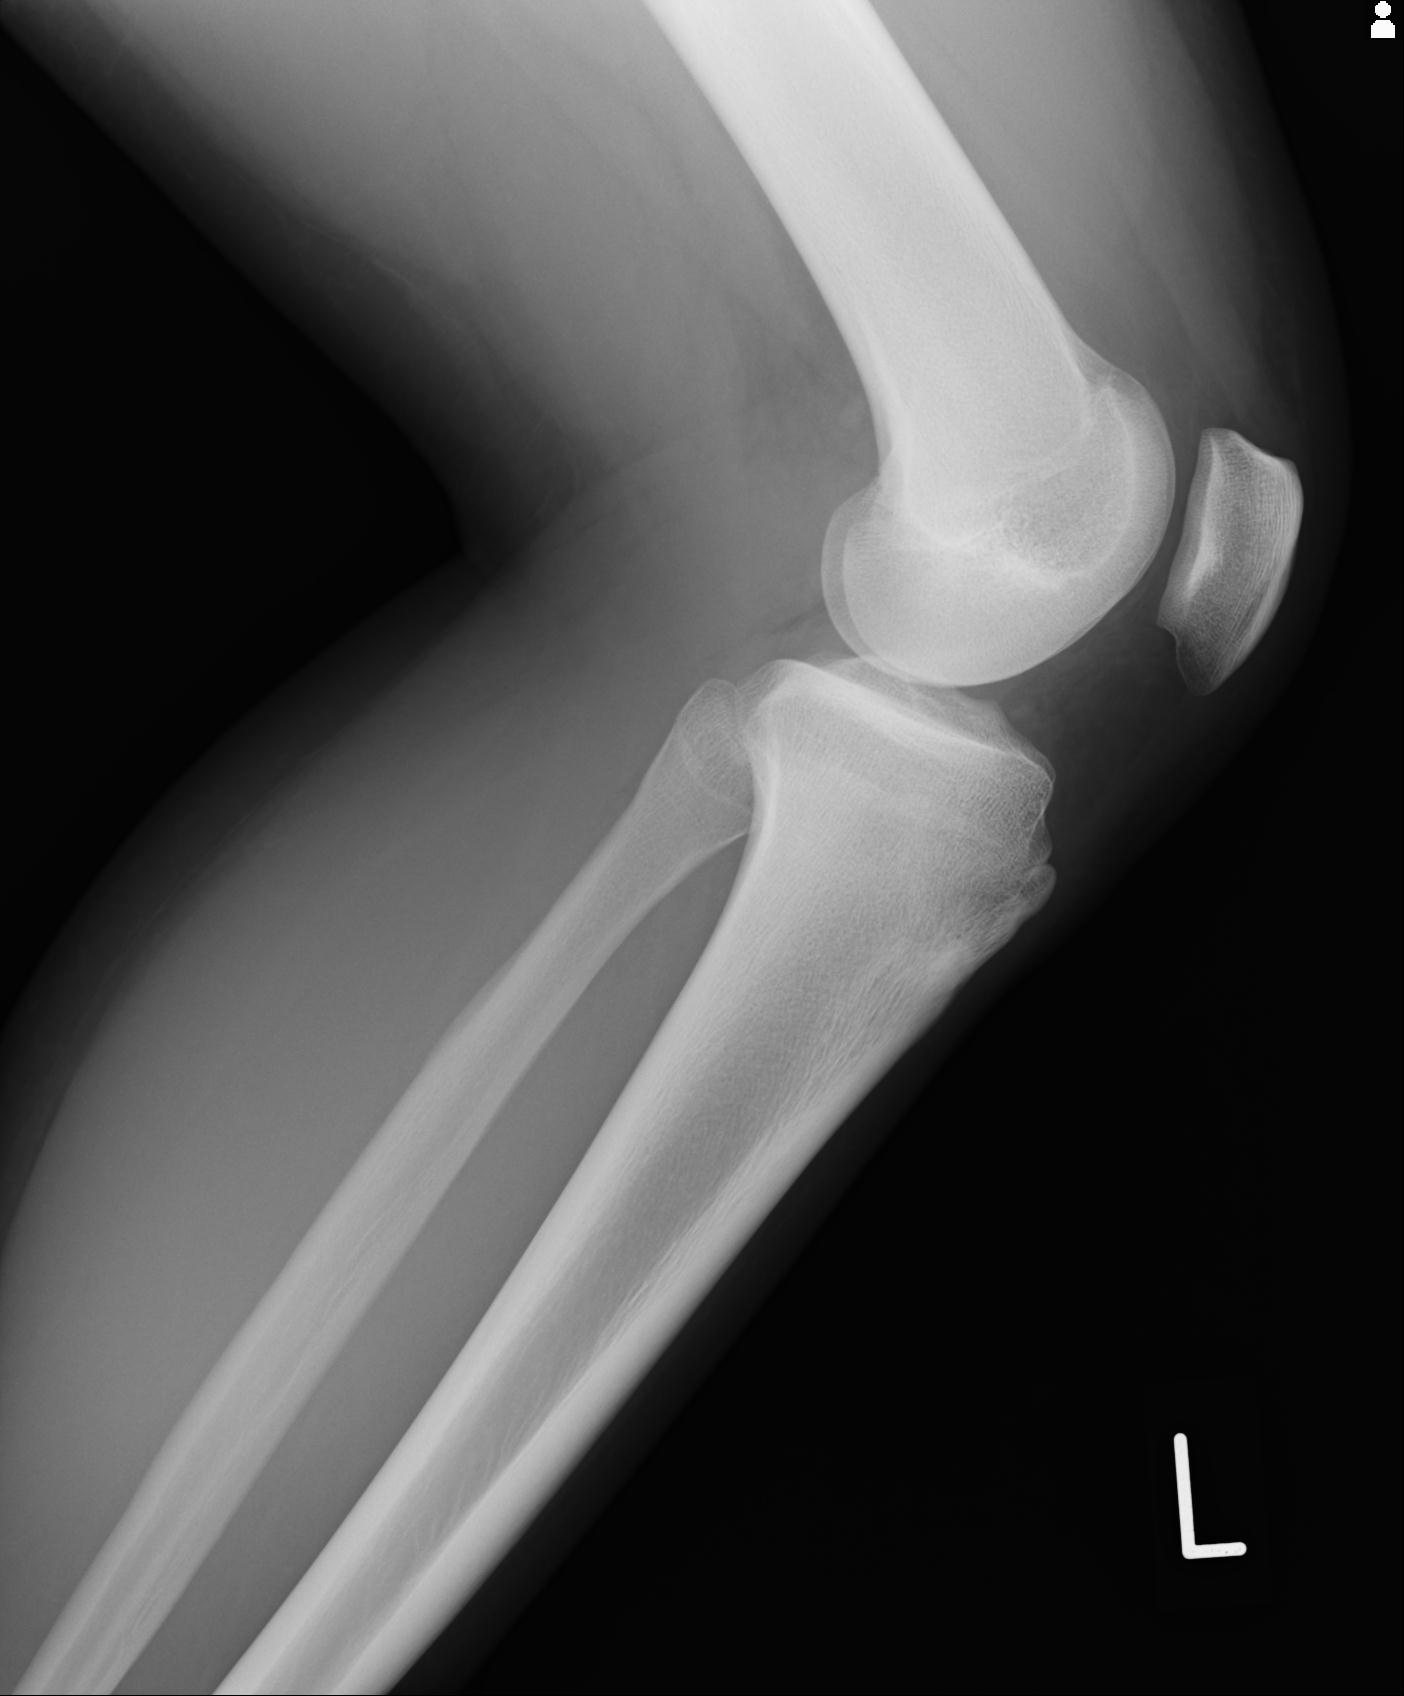

49554 3/13 膝 4R 3/16 4R 1/18 2R 78歳男性 膝蓋骨骨折

91983 11/16 左膝 2R 11/18 2R 55歳男性 脛骨骨切り術